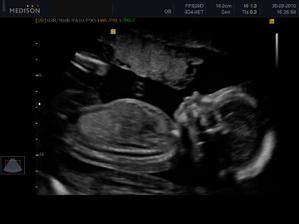

07.06. - (30+4) - utz ve 30tt dopadl dobře, maminka má +9kg

hmotnost - 1435 g

BPD (hlavička od ucha k uchu) - 77 mm

HC (obvod hlavičky) - 278 mm

AC (obvod bříška) - 243 mm

FL (délka stehení kosti) - 59 mm